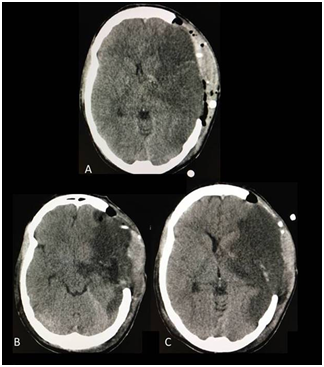

On the fourth day after symptoms onset, the patient depressed consciousness again and installed bradycardia and arterial hypertension. Brain CT scan showed a more configured stroke that caused ventricular system compression and one centimeter midline deviation. In order to reduce undamaged brain tissue compression and diminish intracranial pressure (ICP), a right temporal lobectomy was performed. The infarcted tissue was resected up from the temporal tip to 5 centimeter behind it and in depth up to the arachnoid that separates us from the ambiens cistern. The brain control CT confirmed mass effect improvement (Figure 1). The subsequent evolution was good. One year after surgery the patient is having a plegia of the left upper limb and severe paresis of the lower limb with assistance need for daily life activities (mRS of 4).

Figure 1 A & B: Computed tomography previous to de temporal lobe resection showed the area of stroke as an hypodense area which compression of the homolateral ventricular system, severe midline shift and contralateral hydrocephalus. C & D: Computed tomography after the temporal lobe resection which showed improvement in the mass effect and the absence of complications.